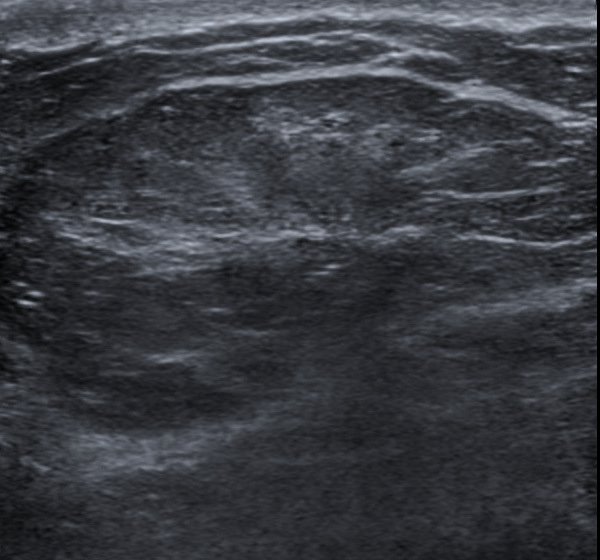

Lipoma of the spermatic cord. (a) US image demonstrates an echogenic …

Liposarcoma – on ultrasound | Image | Radiopaedia.org